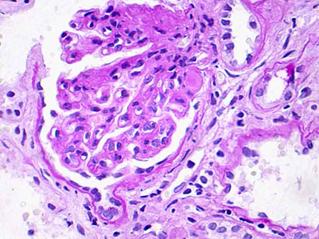

Патоморфология. Гистологические изменения при МН свидетельствуют о главенствующей роли иммунных комплексов, расположенных субэпителиально (между ГБМ и подоцитами). Субэпителиальные (эпимембранозные) иммунные депозиты не приводят к воспалению или привлечению циркулирующих лейкоцитов (нефрит), а в большей степени вызывает комплемент-зависимое повреждение подоцитов и нефротический синдром. Таким образом, при МН происходит утолщение ГБМ без пролиферации клеток. Различаются четыре стадии эволюции МН: стадия I с мелкими субэпителиальными депозитами (светло-серые), стадия II с шипиками, стадия III с новообразованной ГБМ вокруг депозитов и стадия IV с неравномерным утолщением ГБМ и растворением депозитов. (рис.8)

В I стадии клубочки по СМ часто выглядят нормально, так как иммунные депозиты мелкие, отделенные друг от друга. Большое увеличение в лучшем случае может выявить слегка утолщенные периферические ГБМ.

Во II стадии ГБМ иммунные депозиты увеличиваются, ГБМ слегка утолщена. Окраска серебром выявляет типичные шипики — выросты с наружной поверхности ГБМ. Подоцит образует новый материал для ГБМ.

В III стадии белковые (электронно-плотные) депозиты полностью покрываются новообразованной ГБМ и полностью располагаются внутри нее. Вся ГБМ заметно утолщена.

В IV стадии толщина ГБМ становится крайне неравномерной из-за резорбции протеиновых депозитов, на месте которых остаются пустоты (хорошо видимые на ЭМ). В стадиях III в IV обнаруживается все больше и больше полностью или сегментарно склерозированных клубочков.

Рис.8 Мембранозная нефропатия (I-IV стадии) (C.Jenett, 1995)

В. Клубочек с утолщенными капиллярными стенками. В правой части клубочка – инссудативное изменение. Световая микроскопия, PAS х400.